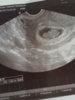

Me käytiin 2.1 uusintaultras, viikot täsmäs 6+1 silloon ja tuota.... Koettiin ehkä yks suurimpia järkytyksiä siinä samalla. NÄITÄ PERKELEITÄ ON KAKS!Ja ei, en oo oikeestaa enää nii järkyttyny ku ensalkuun. Mä vaa jotenki ajattelin et joo, yks siel onneks vaan on, et löytyy kaikki pinnasänkyjä ja vaunuja myöden, mut tuota.... Ei sitte. Miespuplinen tuijotti näyttöä,lääkäriä,näyttöä,lääkäriä ja totes vaan et tuos on yks liikaa näin ekaks yhteiseks,mut vastaan otetaan kummatki. Ite kysyin varmaan kolme kertaa et onkse ny iha varma kahesta,et jos kuitenki vaa ois yks, mut eheeei. Kaikki hyvin,kunhan ei nt ultras kolmatta löydä!!! XD Me siis saatiin tuplauutiset ja vielä kummallakin näkyi sykkeet hienosti. :):)

Kävin varhaisultrassa tänään, pari viikkoa kestäneistä erivärisistä vuodoista huolimatta kaikki näytti hyvältä. Syke näkyi vahvana ja mittojen mukaan 6+6. Vastaa hyvin kuukautiskiertoa.Vuodolle ei syytä löydetty.

Noin pienenä on pituuden mittaus vaikeaa, ja laskettu aika epätarkka. Voi hyvin olla, että seuraava ultra siirtää sinut takaisin elokuulle.Eilinen varhaisultra kertoi pikkuisen valinneen oikean osotteen ja sydänhän siellä sykki voimakkaasti

Melkein viikon verran näytti olleen laskettua nuorempi, eli eilen oli vasta 5+6 ja omien laskujen mukaan olisi ollut 6+5..

Siellähän on jo ihan oikea ihminen!![]()